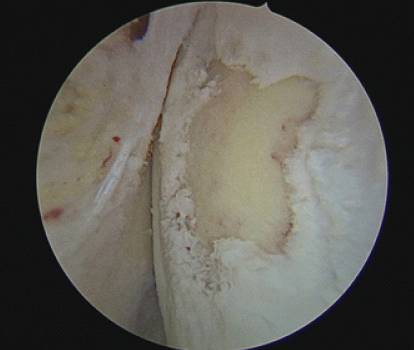

Figure 2: Arthroscopic image showing cartilage defect on the medial femoral condyle.

We initiated the arthroscopic autologous MCI technique with a diagnostic arthroscopy to assess the cartilage defect. Healthy cartilage was then arthroscopically harvested from the defect using a soft tissue shaver connected to an autologous tissue collector (GraftNet: Arthrex), ensuring minimal enlargement of the defect after preparation. The calcified layer was removed, but subchondral drilling was not performed. The harvested cartilage was minced into small fragments, resulting in a paste-like consistency. Minced cartilage was then mixed with platelet-rich plasma (PRP) in a 1:3 ratio. The resulting mixture was loaded into an applicator. Autologous thrombin was generated from additional PRP using a specific device (Thrombinator: Arthrex). After thoroughly drying the joint, the defect was filled with the cartilage-PRP mixture using the applicator. Following a short waiting period, the knee joint was moved through a range of motion to confirm graft fixation over the chondral defect (Fig. 1, 2, 3, 4).